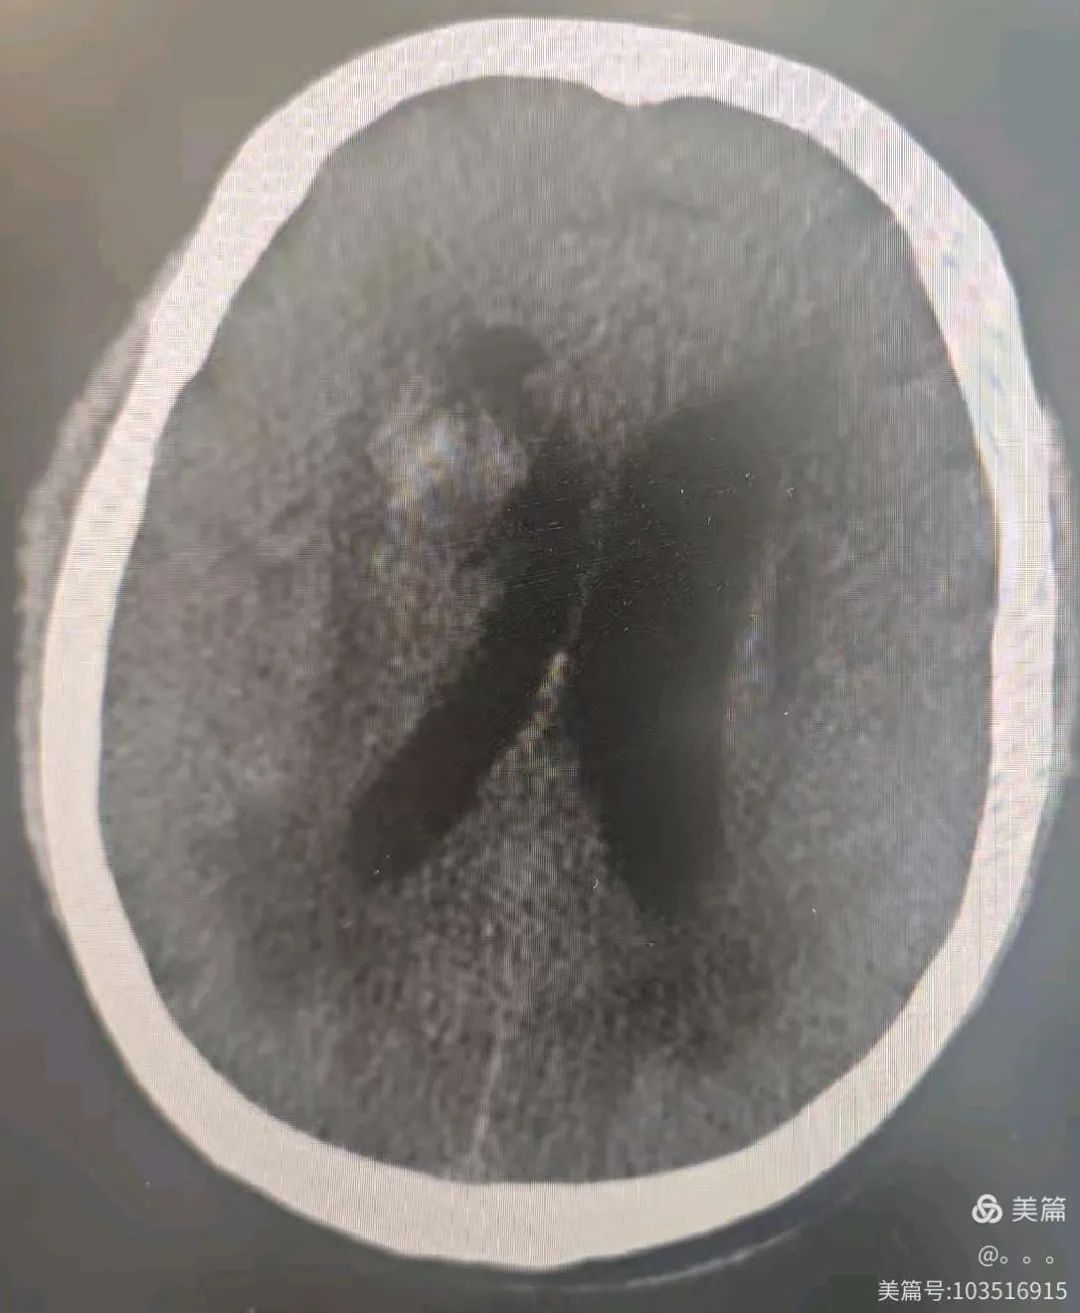

患者樊某,58岁,突发意识不清10小时就诊我院,急诊行CT见右侧基底节出血,破入脑室,右侧脑室前角严重变形。

患者郗某,70岁,突发意识不清2小时就诊我院,急诊行CT见右侧基底节出血,出血量约35ml,并破入脑室形成铸型,病情危重。脑组织受压变形,遂选择机器人精准微创穿刺治疗,同时穿刺脑室及血肿腔。

术后复查CT可见引流管精准的置入了血肿腔及已经变形的脑室,